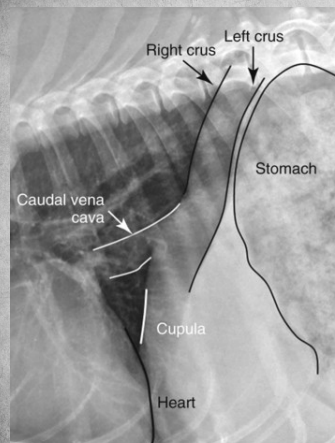

In right lateral:

the diaphragmatic crura are parallel (in left, they form a V)

in right lateral, the caudal vena cava merges with the cranially positioned crus and with the caudal when its left lateral

left lung is seen better in right lateral

heart more egg-shaped in right lateral, rounder in left.

In left lateral: blood vessels of cranial lobes are easier to differentiate.

thoracic lymph nodes may be seen in right lateral but rarely ever in left lateral.